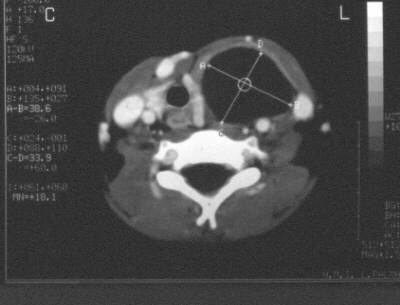

fig. 1

Figura 1. Tomografía axial computarizada (TAC) a nivel cervical. Se puede apreciar un componente quístico predominante.